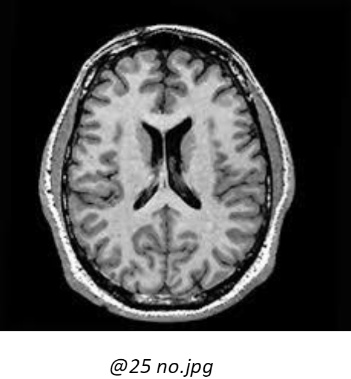

The data comes from a training set made available on Kaggle, more precisely at the following address: https://www.kaggle.com/datasets/navoneel/brain-mri-images-for-brain-tumor-detection There are 253 images available, mainly in .jpg format, although .jpeg and .png are also available. In these images, there are two categories, namely images showing a brain tumour (Yes: 155) and images with no tumour (No: 98). They are all in grayscale. Some additional criteria are noted: